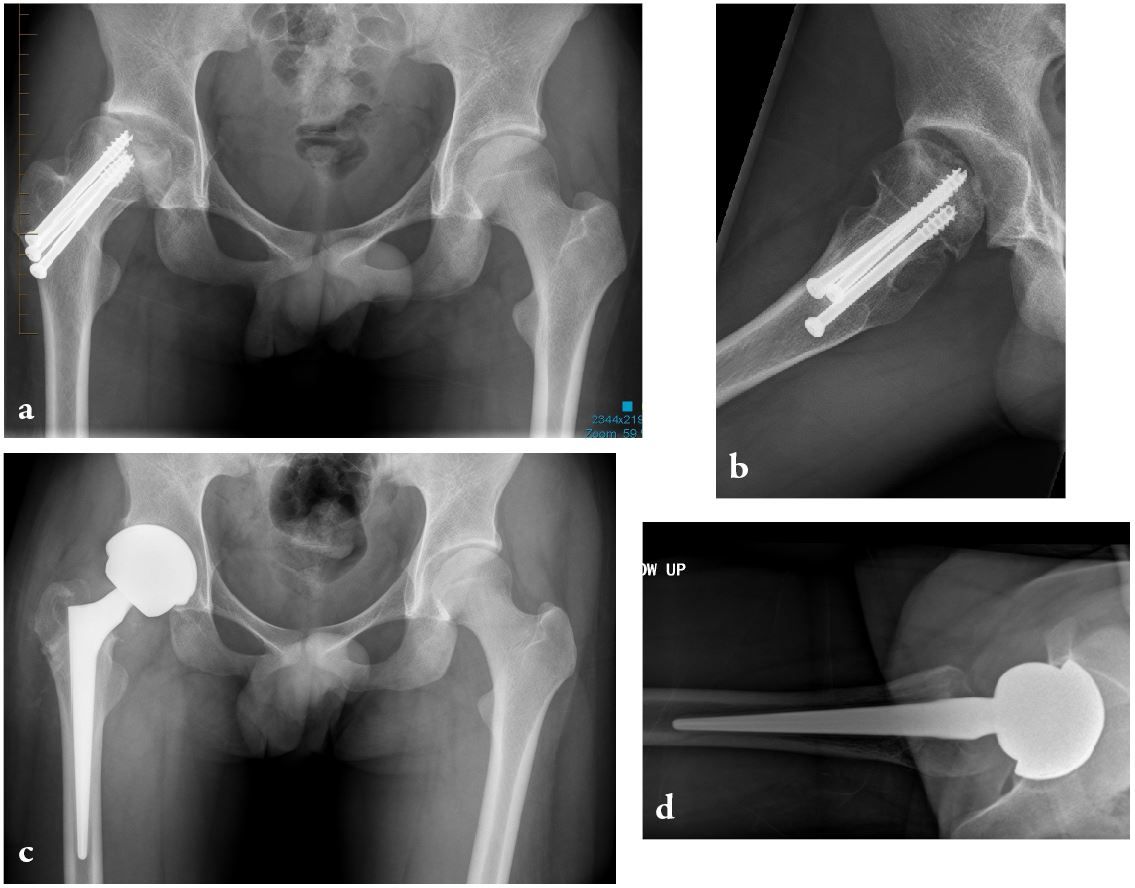

Precise biomechanical reconstruction of the hip is essential for the success of this procedure. Better clinical function and abductor strength can be achieved from optimal femoral offset and restoration of leg length. Otherwise, failure to restore the normal anatomy during THA has been associated with a higher rate of dislocation, muscle weakness, limping, leg-length discrepancy, impingement, and early loosening of the implant (Fig. 4).

To improve the accuracy of the anatomical reconstruction, there is now a greater range of implant sizes, and modular designs have been introduced to give different neck–shaft angles and stem offsets. Nevertheless, anatomical reconstruction of the hip is not always easy. To enable the surgeon to achieve this goal, different implant geometries, an increased range of implant sizes, modular implants and computer navigation systems are now available. We prefer using a fixed neck stem with three different neck angle options to better suit each patient’s specific anatomy, rather than a stem design with a single angle and two different offsets (standard/lateralized). Freed from the risk of instability, surgeons using LDH THA can then better optimize a patient's leg length and offset (Fig. 5). In our experience, a shorter leg is much better tolerated than a longer one. In the cases where the choice between a shorter or a longer head is not clear cut (example: 0mm versus +4mm), we select the shorter one.